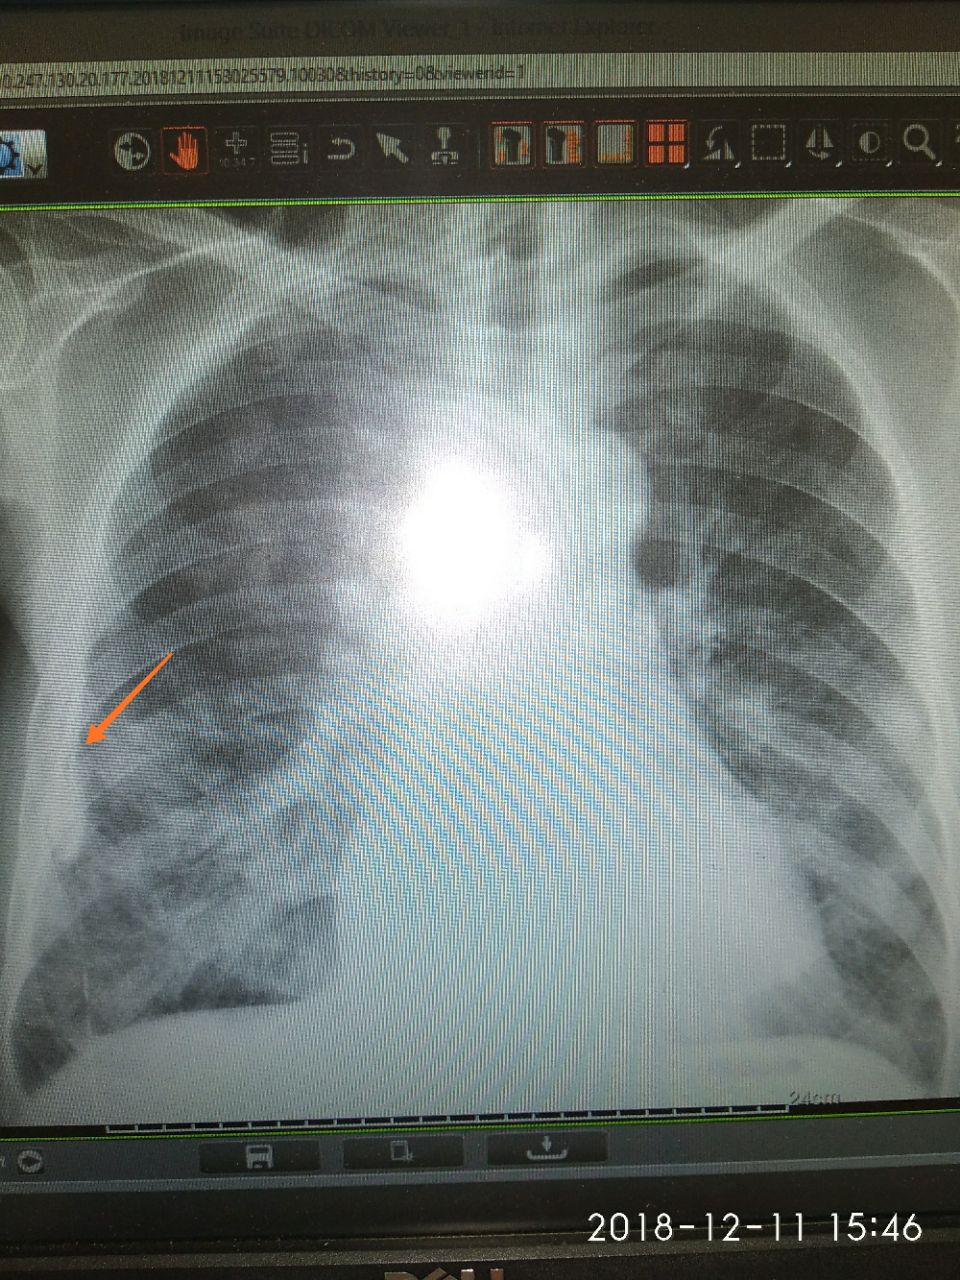

Больной 1940г.р ИБС. Стенокардия ФК2.

06.12.2018 поставил прав н/д бронхопневмония. Снимок сравнивал изм нету.

Фиброз? Бокового нет?

Мне интересуют это

Спайки плевральные паракостально?

Остаточное изменение правостороннего осумкованного плеврита?

Остаточное изменение правостороннего осумкованного плеврита?

Ну.. просто плеврита